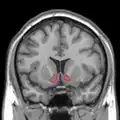

MRI coronal slice showing nucleus accumbens outlined in red